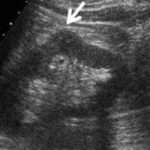

1-Hypertrophied column of Bertin

أعتقد بأن هذا من أهم المتغيرات التي قد يشتبه في كونها ورم. هي ببساطة تضخم لنسيج الكلية parenchyma إلى الداخل sinuses مرورا بين الأهرامات الكلوية medullary pyramids.

يميزه تناسق echogenicity بينه وبين باقي parenchyma بالإضافة لعدم وجود ارتفاع أو تغير ملحوظ في قراءات colour Doppler. غالبا لا يزيد عرضه عن ٣ سم.